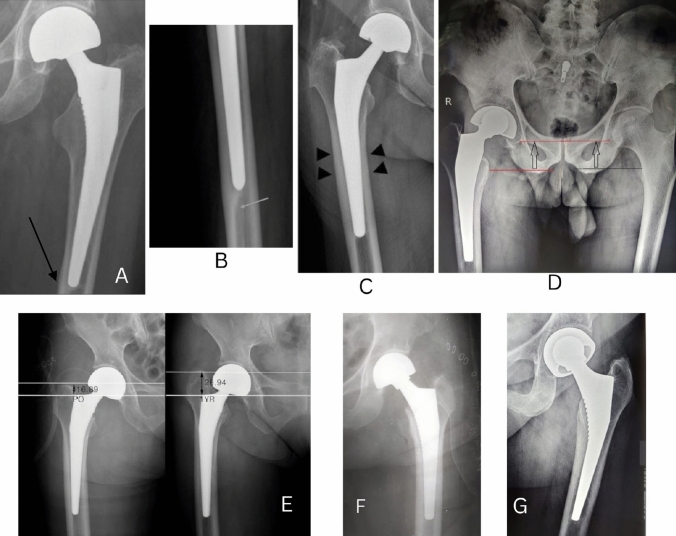

Superficial infection and loosening of the stem were seen in 1.54 percent of the patients, respectively. Limb length discrepancy was seen in 15.38 percent of the patients. Noticed clinical limb length discrepancy was less than 2.5 cm and was not significantly affecting the clinical outcome for all the patients. No cases of dislocation and periprosthetic fracture were noted in our study (Table 1; Fig. 4).

Fig. 4.

A Pedestal formation seen in 76-year-old female at 2-year postop, B pedestal formation, C endosteal bone formation in a 68-year-old female after 1-year post-op, D technique to determine radiological limb length discrepancy, E sinkage of the stem (subsidence)—quantified by measuring the distance from greater trochanter tip to fixed point on the stem, F, G immediate post-op X-ray of a 72-year-old female, 1-year post-op X-ray, showing stress shielding, thickened medial cortex and lucency seen towards the trochanteric area